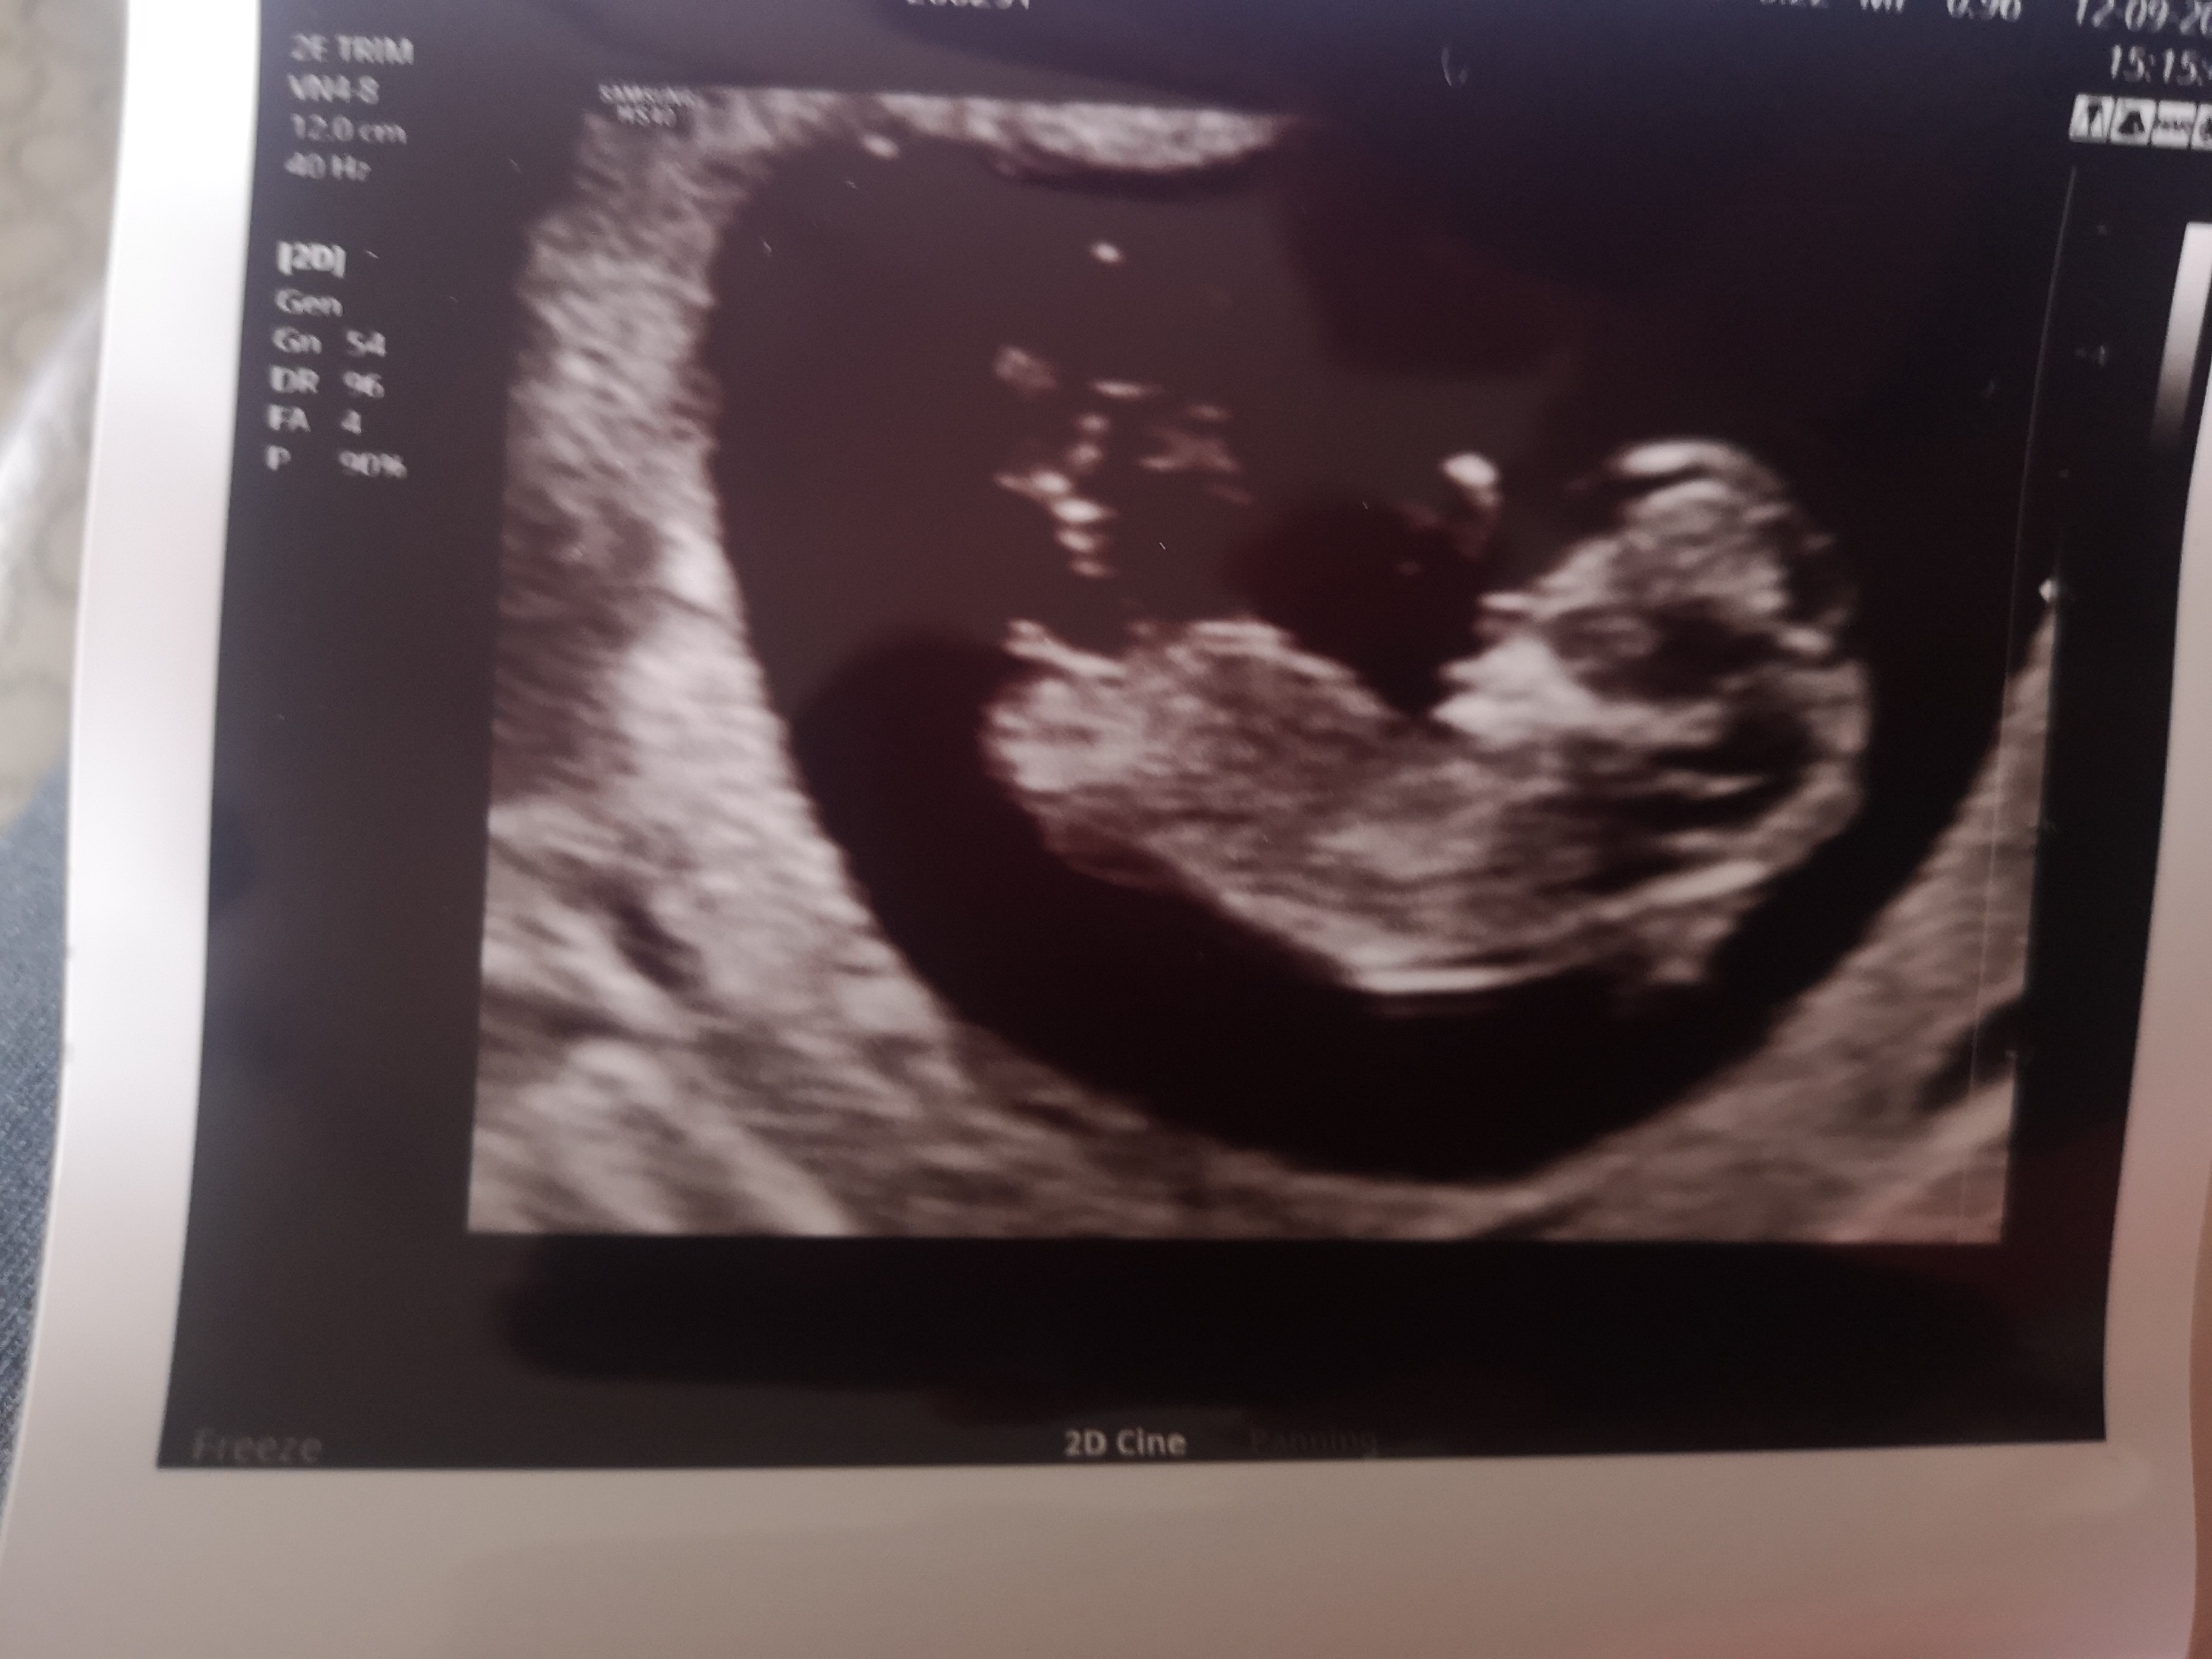

A gdzie jest ten nub a u mnie widzisz?

Załączniki

• IMG_20200912_161750.jpg

IMG_20200912_161750.jpg

1,2 MB · Wyświetleń: 71